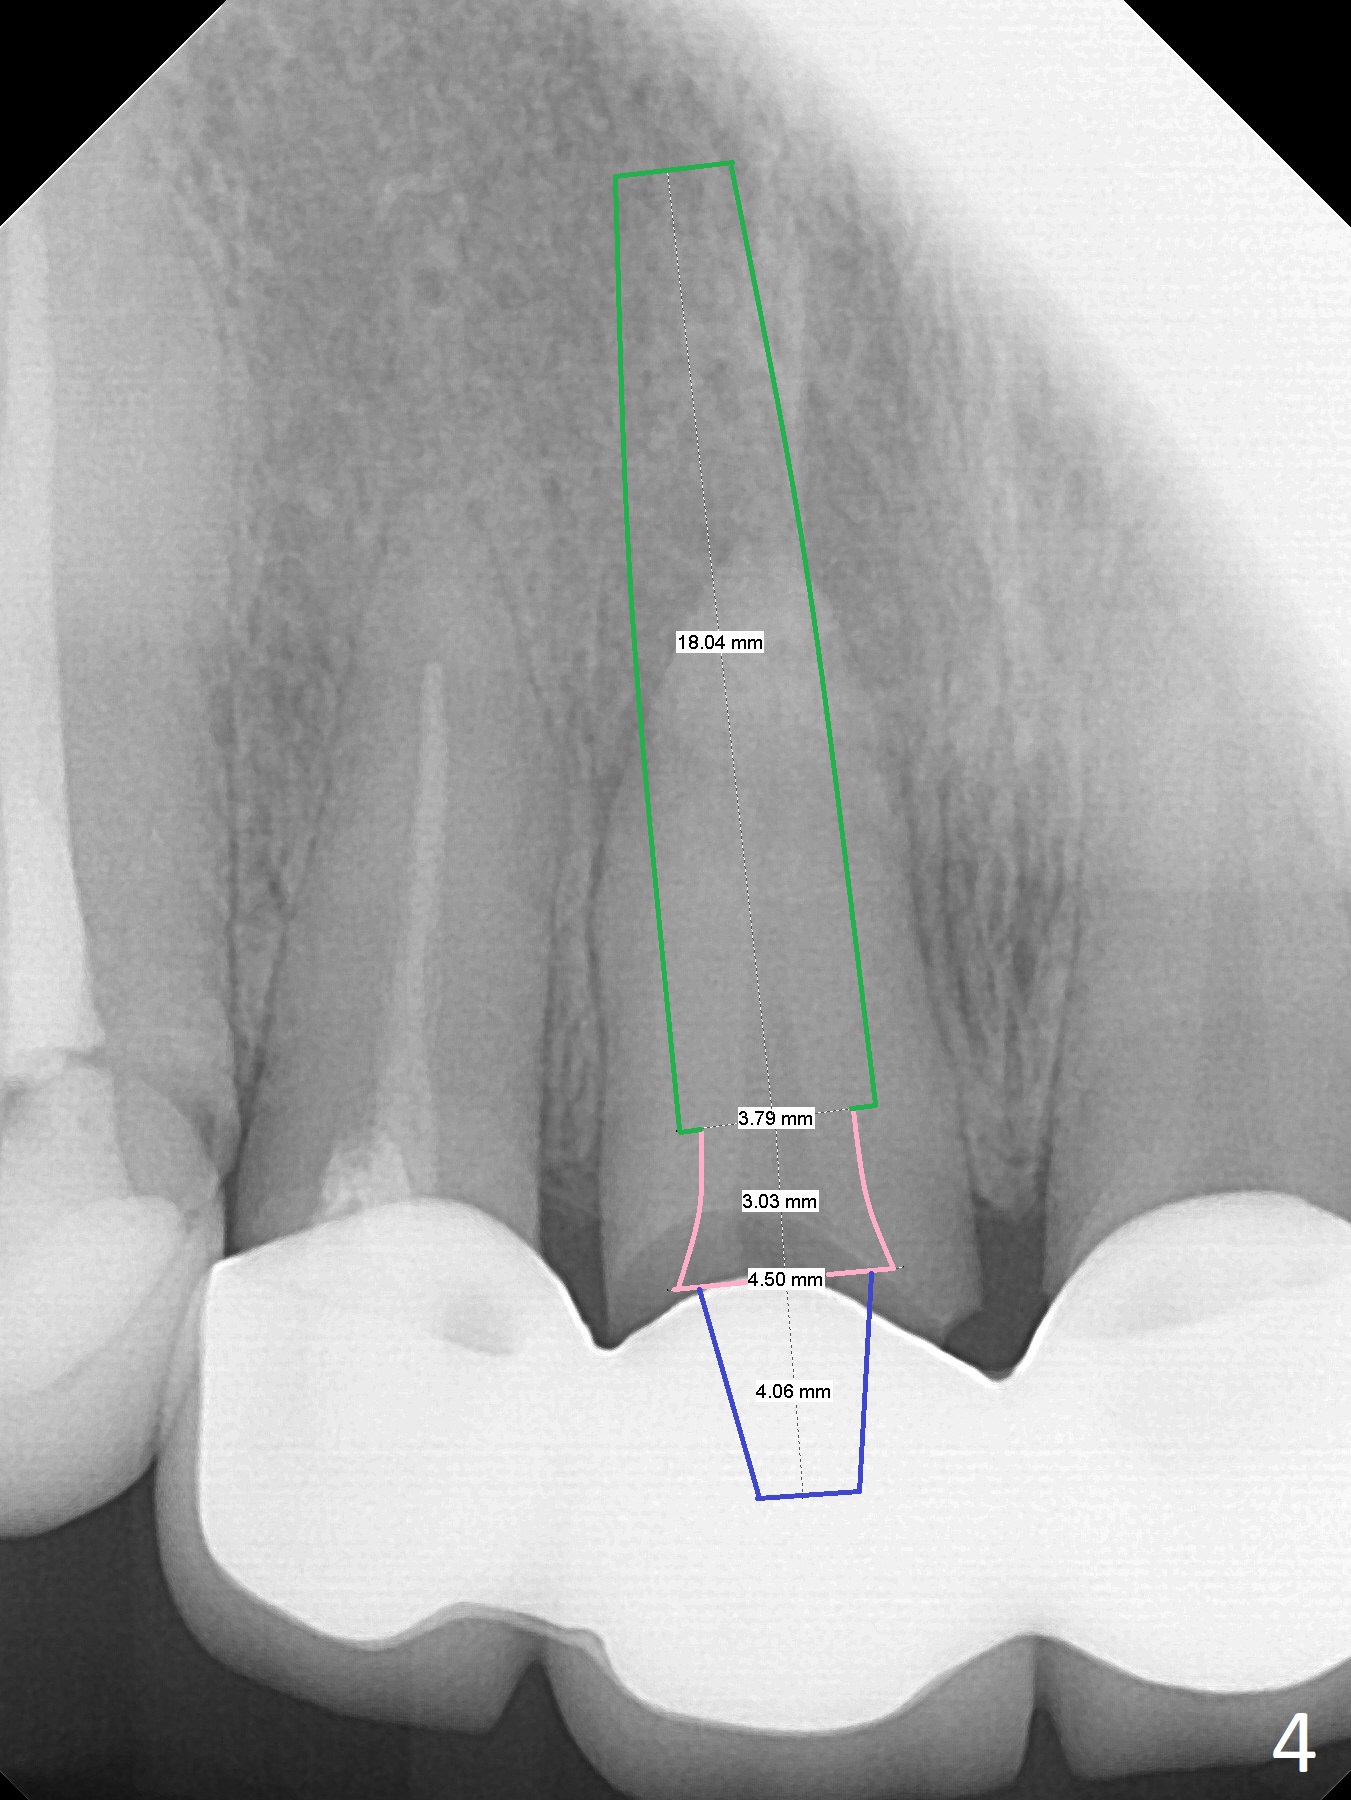

A 55-year-old woman develops apical abscess (Fig.1 yellow outline) at #8 following #7-9 FPD fabrication in China. Since the Incisive Foramen (red outline in Fig.1) is large, initial osteotomy and implant placement will be established not only as palatal as possible, but also mesial (Fig.2 green). IBS system is chosen for this case, because of its 4 mm abutment (minimal prep for provisional), as compared to UF (4.5 mm) and SM (3.9 and 4.8 mm for narrow, 4.8 mm for regular). However, the narrowest and longest IBS implant is 4x13 mm (Fig.2); it barely passes the apical lesion. The 2nd narrowest and longest FC implant is 4.5x15 mm (Fig.3, metal may show off unless subcrestal), as compared to UF (3.8x18 mm, Fig.4) and SM (3.8x14 mm). If the trajectory and osteotomy is initiated ideally, use IBS. Otherwise switch to UF. The FPD will be sectioned.